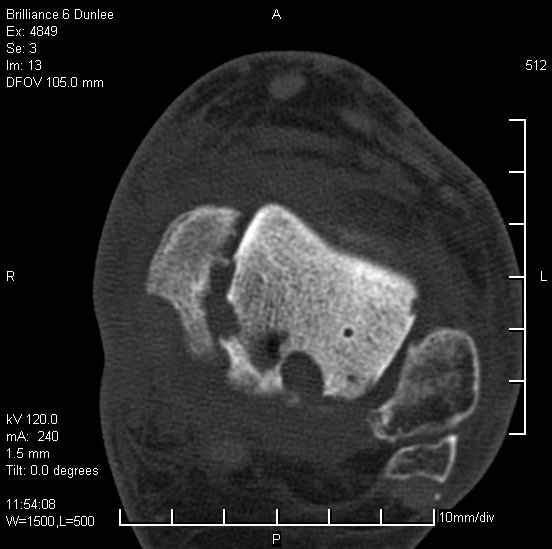

На лечении находится пациент 35 лет. Травма в сентябре 2008 г.- открытый вывих таранной кости

В день травмы ПХО, вправление вывиха, трансартикулярная фиксация. Рана зажила первично. С января нагрузка на конечность. С конца апреля- болевой синдром. На рентгенограммах и КТ признаки ас. некроза таранной кости, артроз подтаранного и голеностопного суставов.

У больного тотальный ас. некрох блока таранной кости, заинтересованы голеностопный и подтараный суставы. Эндопротезирование маловероятно на некротизированную кость. Изолированный подтаранный артродез таран не спасет.При артродезе всю некротизированную кость придется убрать.А далее замещение либо за счет большеберцовой кости, или удлинение на регенерате.